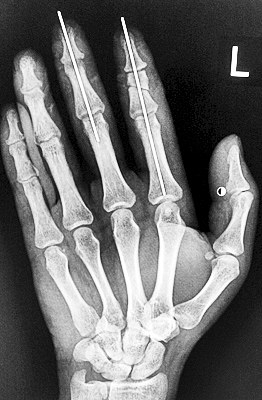

術(shù)后X光顯示,骨骼對位良好。

最終,盧微波和團隊找好了需要的血管和神經(jīng),做好標記后,開始固定食指骨骼、吻合肌腱,最后在顯微鏡下用直徑20微米的無創(chuàng)顯微縫合線開始吻合血管和神經(jīng)。

在經(jīng)過兩個多小時手術(shù)后,早上8時許,盧微波下令松止血帶,數(shù)十秒后男子蒼白的食指逐漸紅潤起來,食指在離體10個小時后恢復血運。

緊接著,盧微波又開始中指再植手術(shù)。上午10時許,中指在離體12小時后也成功恢復血運。